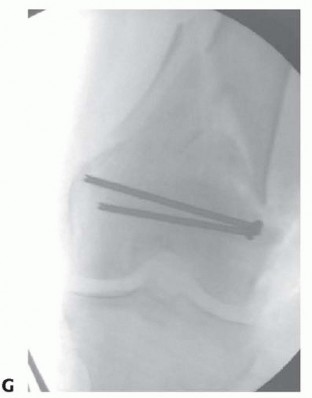

--- - FIG 12 • A. Lateral radiograph of patient with a grade II open distal medial femoral condyle fracture (type B3). The Hoffa fragment is outlined. B. Postoperative radiograph after fixation with headless screws, buried underneath the subchondral bone. Soft tissue dissection should be limited. Adequate exposure is important to anatomically restore the articular surface. Restoration of limb “anatomy” must be accomplished and allow early range of motion. Stable internal fixation and length and sizes of implants should be templated. Radiographs of the injury can be templated with implant templates to ensure that proper lengths are available. A tentative plan of the fixation construct can be drawn on the image. Additionally, “preop planning” of the operating room should be performed; this includes a discussion with the operative team about the positioning and equipment needed for the procedure. The need for bone grafting or the use of bone graft substitutes should be assessed. Fracture fragments and the anticipated fixation construct should be templated. The surgeon should check for coronal plane fractures of the condyles (also known as Hoffa fragments) (see FIGS 5C and 6). 476

### FIG 5 • A-C. Patient with a spiral distal-third femur fracture that appears to be extra-articular. A. In the AP radiograph, the knee is not fully visualized. B. A dedicated knee AP radiograph shows the spiral distal-third femur fracture. Note the intra-articular injury and the gap at the fracture (arrows). C. Lateral view of the knee. Again note the coronal fracture of the medial femoral condyle (type B3). D-F. Plain radiographs of a patient with a grade II open distal femur fracture. G,H. Patient with a dosed femur fracture that was initially thought to be extra-articular. 470

### FIG 6 • A. Axial CT image of patient in FIG 5A-C confirming the type B3 fracture of the medial femoral condyle. B. Axial CT image of the patient in FIG 5D-F. C-E. CT images of the patient in FIG 5G,H show the nondisplaced intercondylar split as well as the low lateral fracture line and extensive posterior metaphyseal comminution (type C2).